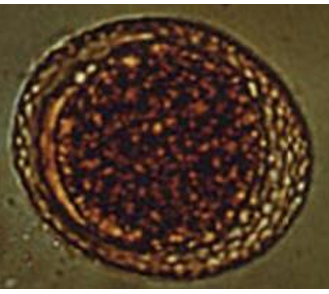

A. caninum

Ovum